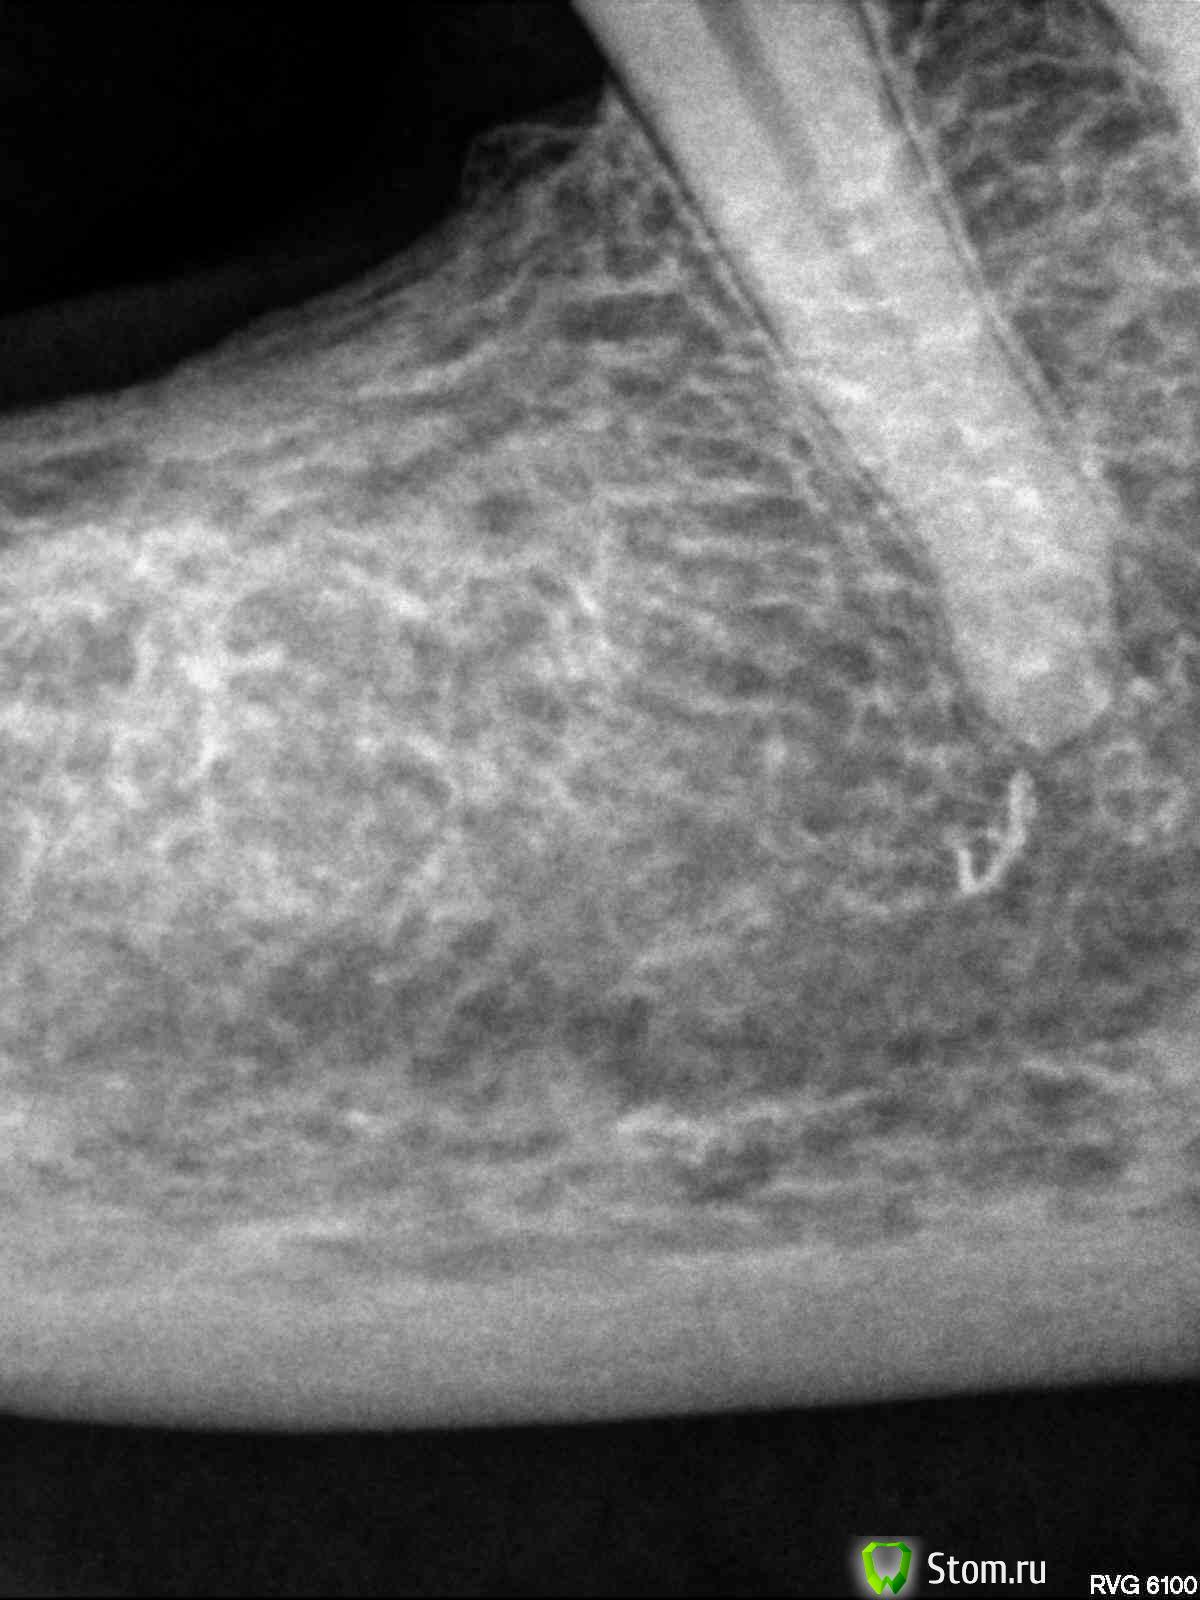

evm Опубликовано 26 апреля, 2012 Поделиться Опубликовано 26 апреля, 2012 Здравствуйте! Проблема: на живых 3-ке, 4-ке и 5-ке внизу справа стояла металлопластмасса (мост полуразрушенный, травмировал десну). Хотела менять осенью, но, поскольку стали появляться ночные ноющие боли (терпимые, но с Метрогилом-Дента), решила не тянуть. 28 марта под анестезией депульпировали все три зуба и запломбировали. Когда пломбировали, в 5-ке чувствовала боль и потом было больно по ней стучать. 10 апреля должна была уже начать протезирование (металлокер. на штифтах). 3 и 4 молчали, а 5-ка все время мозжила и к 10 апреля поддала жару- воспалился лимфоузел и боль усилилась, а также появился болезненный участок рядом с корнем. Канал открыли, положили лекарство под временную пломбу, через три дня - повторили. Терапевт все время убеждала, что с зубом полный порядок. Другой врач сказала: или аллергия, или периодонтит на маленьком учаске (в узкой щели), где тяжело достать (это мой вольный пересказ ее слов). Боль если и утихала, то очень медленно и зуб чувствовала всегда. Через три с половиной недели (22 апреля) взбесилась 4-ка, больно было толкать языком и болела больше, чем 5 (возможно, из-за замерзших накануне ног). Поскольку первый врач считал, что у меня все вылечено, пошла ко второму. Та сделала укол (антибиотик плюс ультракаин, на лидокаин была раньше алергия - крапивница по всему лицу, как герпес), вспомнили мы про физлечение, и в своей поликлинике стала делать дэнос и атерм.УВЧ. Опять пошла алергия, сначала думала - на инъекцию, а теперь думаю, может быть и на ток - пузыри кучно в месте контакта с электродом, а на лидокаин до этого - по всему лицу. Пока все отменили. Зубы периодически о себе напоминают. По 4-ке стучать больнее, чем по 5-ке. 4-ку не открывали. Аллергия (тогда почему 3-ка молчит?) или хр.периодонтит? На снимке видно, что у 5-ки пломб.материал вышел за верхушку, но, скорее всего мозжащая (а иногда пульсирующая, но спать дающая) боль не из-за этого? Ссылка на комментарий

Magdalena Опубликовано 29 апреля, 2012 Поделиться Опубликовано 29 апреля, 2012 Если подвела антисептическая обработка каналов, что Вы предлагаете делать мне? Перелечивать не только 5 зуб, но и 4. Видимо, диагностика по снимкам затруднена, пока нет патологии в виде гранулем и кистОбычные прицельные снимки - двухплоскостные, по ним не всегда видно локализацию воспалительного процесса, ход и количество корневых каналов. Поэтому для более точной диагностики существует компьютерная 3Д - томография (трехмерная), на ней зуб можно "покрутить" и посмотреть со всех сторон, а также в поперечном срезе (это помогает определить кол-во и ход каналов). Ссылка на комментарий